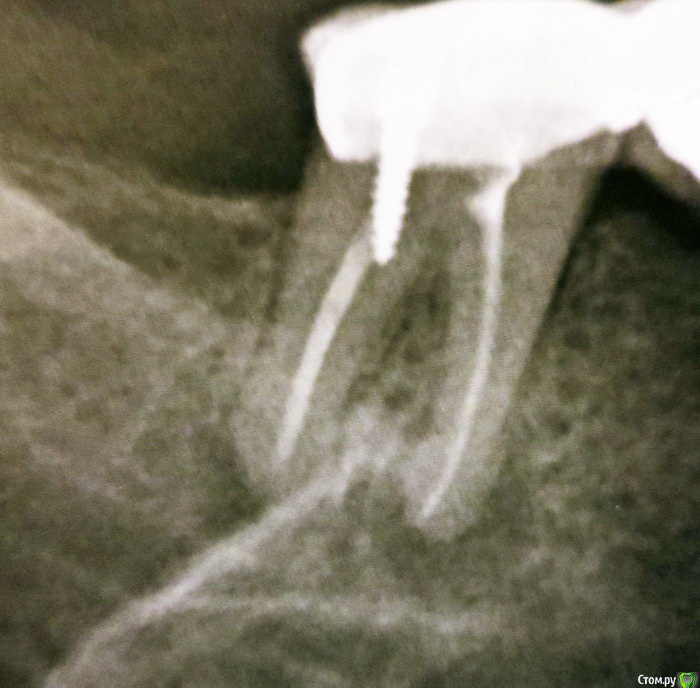

полосатая Опубликовано 6 июля, 2016 Автор Поделиться Опубликовано 6 июля, 2016 Снимок зуба до лечения. Ссылка на комментарий

полосатая Опубликовано 6 июля, 2016 Поделиться Опубликовано 6 июля, 2016 Здравствуйте.Позавчера стоматолог раскрыл 7-ку на нижней челюсти.На снимке обнаружилась(случайно )гранулема на корне.Зуб был опорным для моста, был давно депульпирован,каналы запломбированы гуттаперчей,не беспокоил,мост стоял лет 15. Врач удалил вкладку, каналы почистил,промыл,поставил какое -то лекарство и временную пломбу. Сначала зуб немного ныл, а со вчерашнего вечера уже ломит челюсть и отдает висок,увеличился подчелюстной лимфоузел, Десна отечная, красная. Одна таблетка кетанов снимает боль на 1-2 часа.Полоскания соль+сода+йод не помогает.До этого доктор мне лечил гранулему на другом зубе тоже депульпированном и запломбированном гуттаперчей , но такой реакции не было. Не могу дозвониться к своему врачу целый день, телефон отключен!?Следующий прием назначен на вторник. Прошу помощи. Выпила уже 8 таблеток кетанов по 10мг.Кетонал 100мг. вообще не помогает.Вторую бессонную ночь не переживу...Может нужно удалить эту временную пломбу и полоскать ? Ссылка на комментарий